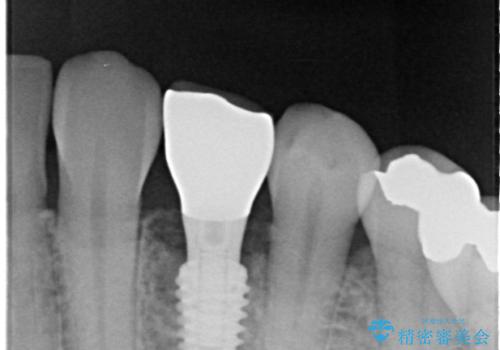

治療は計画通りに進み、約3か月で最終補綴まで完了。

見た目だけでなく、しっかり噛める機能も回復し、患者様にも大変ご満足いただけました。